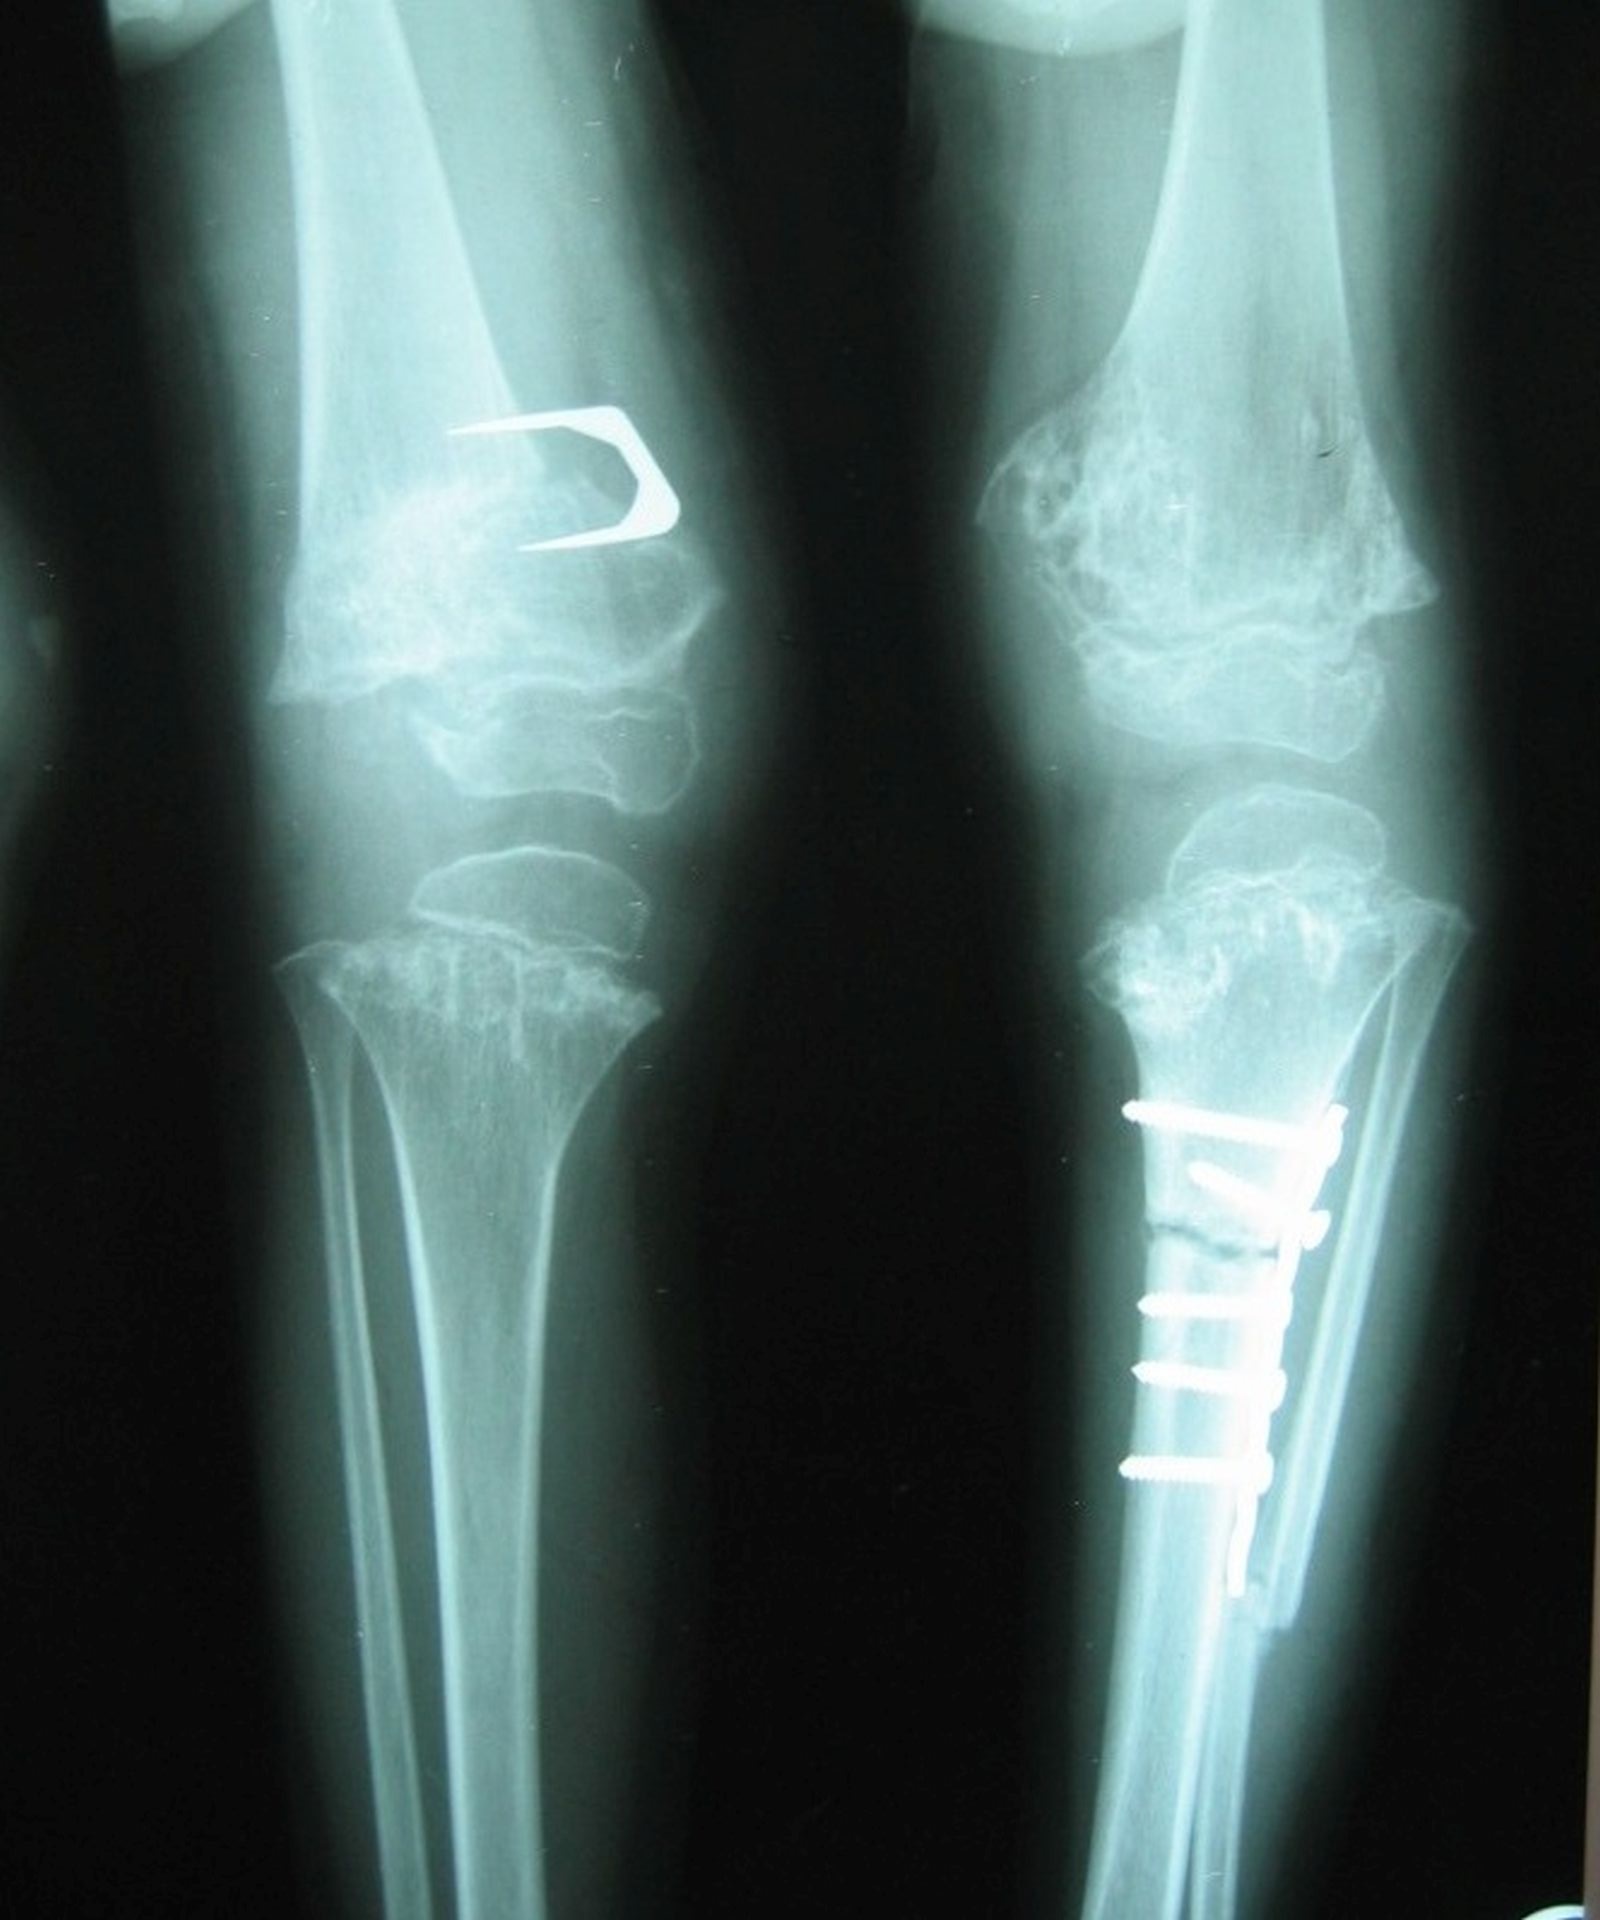

After marrying my wife in the United States on completion of my postdoctoral studies, we returned to Australia, where our daughter was born a few years later. One day, our petite ten-month-old infant was trying to pull herself up using a chair leg for support. My wife heard a popping sound and a whimper as she flopped back onto the floor. X-rays indicated she had snapped a tibia.

I would estimate that aborting them would have prevented an upper limit of some one hundred fractures. Treating a fracture is among the cheapest interventions in modern medicine: Perhaps we would have saved the cost of a few cartons of plaster-of-Paris bandages, several dozen calico arm slings, and several cases of radiography film. For the small number of fractures that required surgical correction, we could have saved the cost of a dozen or so brief hospital stays. For a wealthy state like ours, this seems a trivial sum.